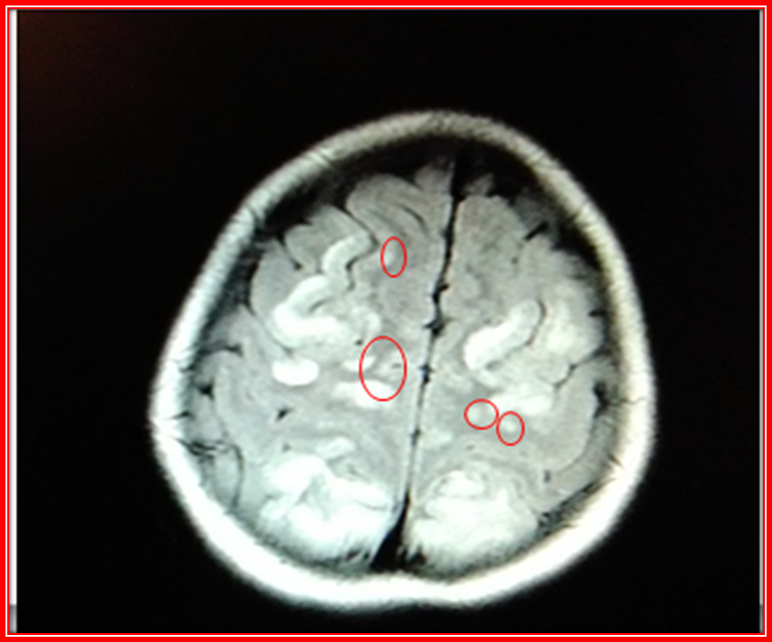

The following are images of Simple Brain Magnetic Resonance, of the patient of the case already discussed.

Brain Magnetic Resonance Simple cut T2.@anaestrada12

CT scans show changes in the signal intensity of hypointense behavior in T1 and Hyperintense in T2 with perilesional edema, including cortical region, sub-cortical frontal lobe, parietal and bilateral occipital.